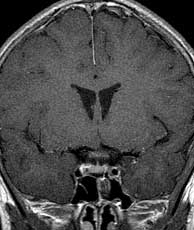

T1 coronals post-gad 15 months later

Findings:

Bright signal lesion posterior and inferior to the optic chiasm unchanged compared to 15 months earlier.